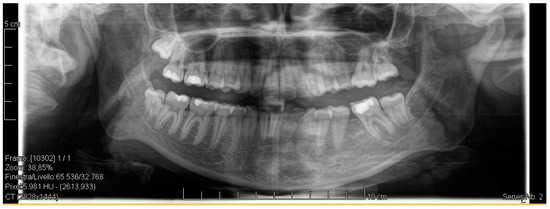

Figure 1.

Pre-treatment radiograph of the patient. The first two left molars appear irreparably compromised by destructive caries.

A case of CA therapy without attachments and without the aid of hybrid elements has been documented. The patient, an 18-year-old woman at the beginning of treatment (October 2021), signed written informed consent to orthodontic treatment and authorized the use of her anonymized treatment data, including photos, X-rays and virtual models of the dental arches. She needed to rehabilitate two edentulous areas corresponding to first maxillary and mandibular molars, both on the left side, assessed as irrecoverable for destructive caries at the time of the orthodontic evaluation (Figure 1). The patient refused rehabilitation with prosthetic implants and orthodontic treatments with fixed or hybrid fixed-removable therapy. Orthopanoramic (Figure 1) and lateral teleradiography of the skull (Figure 2) were acquired to make the necessary assessments. The cephalometric examination was performed using the Cephio© Cephalometric Analysis artificial intelligence driven platform (Cephio sp. z. o. o. [Ltd.]). Her skeletal class II malocclusion was due to maxillar and mandibular retrusion (SNA 80°, SNB° 74.6°, ANB 5.4°, SNPog 76.2°). She had “long face” (OP-SNP 21.1°), a posterior inclination of the jaw (MPGoGn- SNP 35.4°), slight hyperdivergence (FMA 26.2°), with pro-inclined lower incisors (1-NB 28.4°, IMPA 96.1°) and retroclined upper incisors (1-NA 14.1°, FMIA 57.7°). Overjet and overbite were severely altered (6 and 7 mm) (Table 3). Orthodontic treatment started 4 months after the first left maxillary and mandibular molar extractions. Intraoral and facial photos were captured (Canon© Coolpix A900, Canon, Tokyo 146-8501, Japan). Dentally, she had a first molar and canine class on the right side, and a first canine class on the left side in which the molar class was no longer assessable (initially it was a first class); however, a partial reduction in edentulous spaces was observed due to the movement of adjacent teeth (Figure 3) and lower incisors were moderately crowded. Precision silicone impressions (Elite HD+ Putty Soft Normal and Elite HD+ Super Light Body, Zhermack SpA, Badia, Italy) were taken using the double technique. Then, a virtual setup of the treatment with CAs was developed to evaluate its feasibility. It showed full closure of edentulous spaces and was also discussed successively with the patient. The orthodontist clarified there were no data from the literature (at that time) to support the successful movements required with only CAs. The orthodontist and patient started treatment by agreement. The informed consent to treatment was signed. It also covered clinical re-evaluation with solutions less favorable to the patient’s preferences if the results in the middle of treatment had been clinically unsatisfactory or unfavorable. The orthodontist explained the need to intercept any treatment complications to the patient. This also related to the predictability of intermediate results for medico-legal reasons, for the mutual protection of her as a patient and of the orthodontist as a professional responsible for the therapy. Initial and final virtual models were superimposed to evaluate the movements obtained (Maestro 3D©, AGE Solutions S.r.l., Pontedera- Pisa, Italy). At the end of the therapy, new X-rays were requested and new intraoral and extraoral photos were recorded.